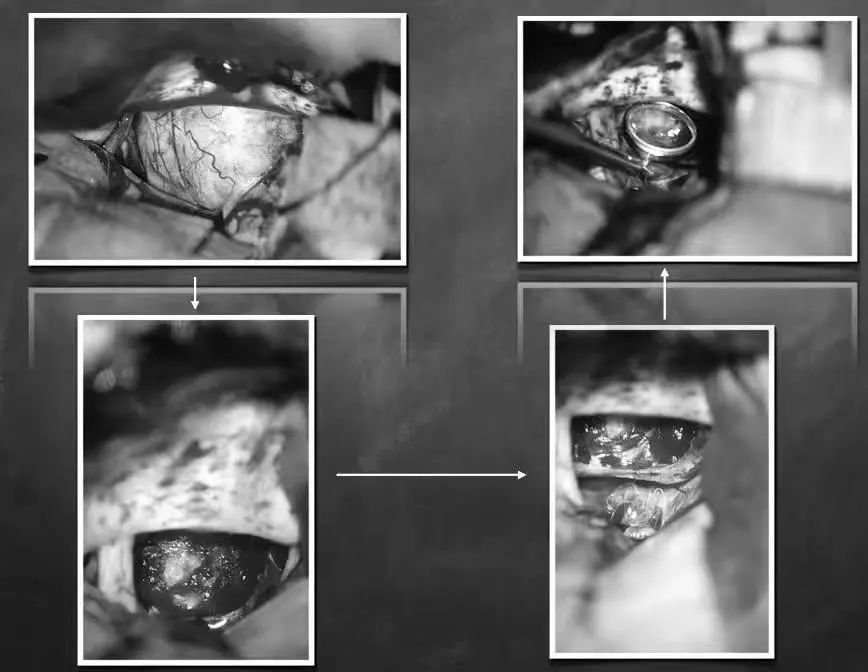

鲁特卡教授很快对安达的病情进行全面分析,最终确定了一个手术方案,在与安达家人进行沟通并取得同意后,一场承载着一个小女孩未来的手术正式开始了。

在手术室外等待良久,安达父母听到了一个好得不能再好的消息:“手术顺利,肿瘤已经被安全全切了!”